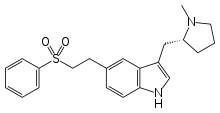

Eletriptan | 3-{[(2R)-1-methylpyrrolidin-2-yl]methyl}-5-[2-(benzenesulfonyl)ethyl]-1H-indole | 143322-58-1 |